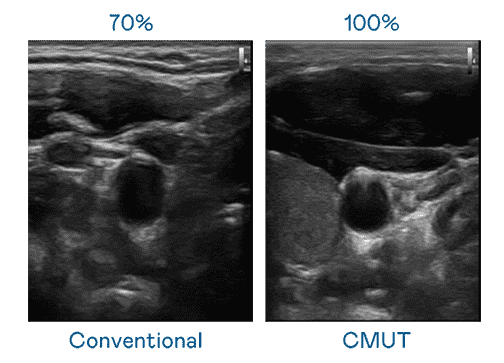

CMUT 技术是一种用电容式微机电元件来产生超音波讯号的技术。。。。与传统 PZT 压电式技术相比,,,CMUT 频宽增加 30%,,,,更宽频的超音波讯号让影像解析度大幅提升,,是实现高影像品质医疗超音波扫描、、促进精准医疗发展的关键技术。。。

大频宽带来超清晰影像

超音波影像的解析度高低,,,首先取决于探头能发出的讯号频宽。。。龙门国际 CMUT 可提供高清晰的超音波讯号,,,,提供高频宽、、、高灵敏度、、、影像纹理细节更高的超音波影像,,,,协助医护人员缩短影像判读时间及利用精准的医疗影像进行诊断。。。